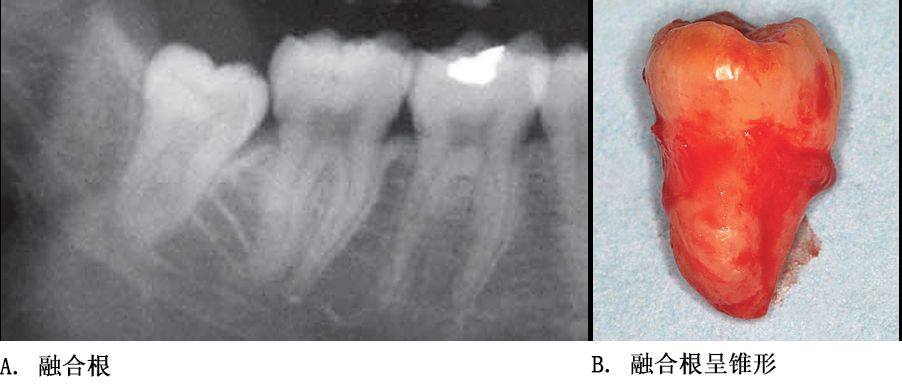

单根牙、根分叉不大者、合并根、融合根、特短根、锥形根阻力较小。若根尖区向远中弯曲、无弯曲或根尖未形成,则阻力也较小。